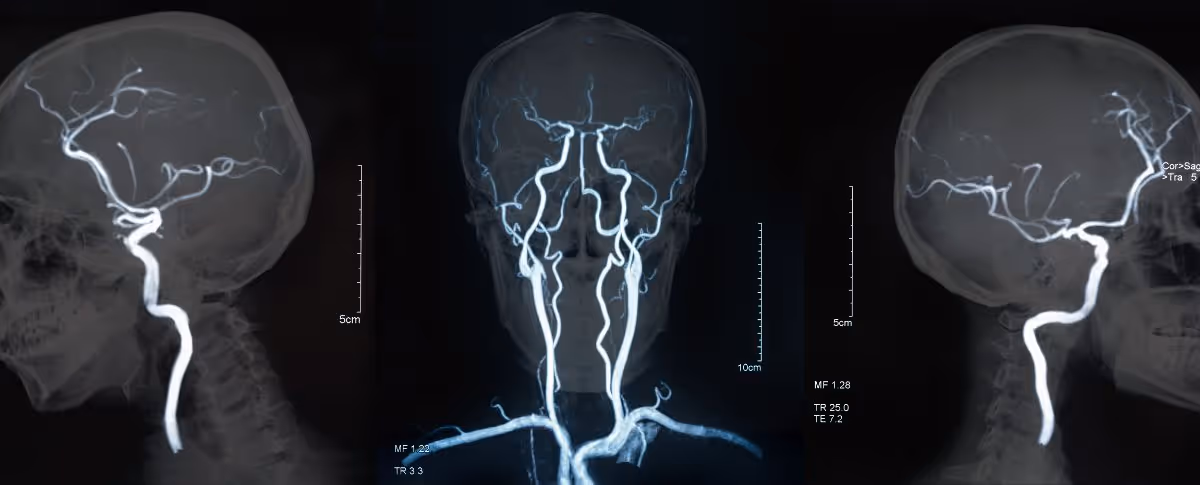

ตรวจ MRA คือ การตรวจหาความผิดปกติของหลอดเลือดและระบบไหลเวียนโลหิต โดยที่ไม่ก่อให้เกิดการบาดเจ็บต่อร่างกาย (non-invasive technique) ซึ่งช่วยในการตรวจวินิจฉัยความผิดปกติของหลอดเลือด เช่น ภาวะหลอดเลือดแข็งหรือลิ่มเลือดอุดตัน ในบางกรณีอาจจำเป็นต้องใช้สารเปรียบเทียบความชัด (gadolinium-based MR contrast agents) ร่วมด้วย เพื่อเพิ่มความคมชัดของภาพและการตรวจวินิจฉัยอย่างแม่นยำ

MRA คือการใช้คลื่นแม่เหล็กไฟฟ้าและคลื่นวิทยุในการช่วยสร้างภาพหลอดเลือดและระบบไหลเวียนโลหิตออกมาเป็นภาพ 2 มิติหรือ 3 มิติ ซึ่งเทคนิคการตรวจนี้จะช่วยในตรวจหาความผิดปกติของหลอดเลือด

MRA ถือเป็นเทคนิคหนึ่งของการตรวจ MRI ที่เน้นการสร้างภาพของหลอดเลือดและระบบไหลเวียนโลหิต เพื่อวินิจฉัยภาวะต่าง ๆ ที่เกี่ยวข้องกับหลอดเลือด เช่น หลอดเลือดตีบ หลอดเลือดโป่งพอง หรือการตรวจหาก้อนเนื้องอกในหลอดเลือด

การตรวจ MRA ช่วยให้แพทย์เห็นภาพหลอดเลือดในร่างกายอย่างละเอียด ตรวจพบความผิดปกติของหลอดเลือด วินิจฉัยและวางแผนการรักษาได้อย่างเหมาะสม ช่วยติดตามผลการรักษาโรคหลอดเลือด และประเมินความเสี่ยงของโรคหลอดเลือดสมองและหัวใจ